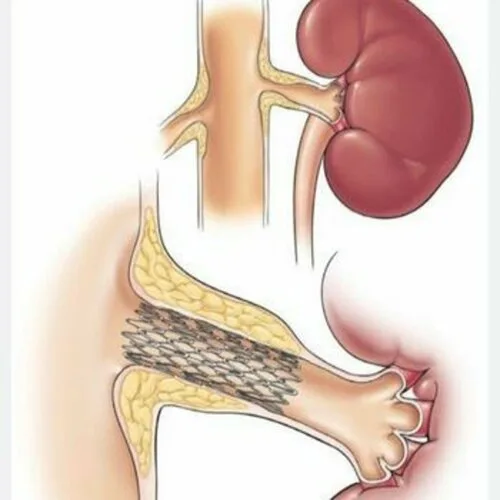

- تنگی عروق کلیه

- نفروپاتی دیابتی

- انسداد شریانهای اندام تحتانی(PAD)